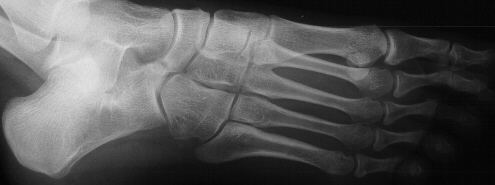

This

condition is usually thought to be autosomal dominant inheritance

with variable penetrance.

The

etiology of the above problem appears to be a defect in segmentation

and differentiation of the primitive mesenchyme

A

conservative treatment of casting and orthotic use has no scientific

basis of support for this condition.

etiology of the spastic flat foot is a neurologic response to

inflammation in the subtalar joint causing spasticity of the peroneal

muscles.

Because

additional coalitions occur in 15 percent of the feet with a talonavicular

coalition, a CT scan of the talocalcaneal joint is required prior

to excision of the talonavicular bar.